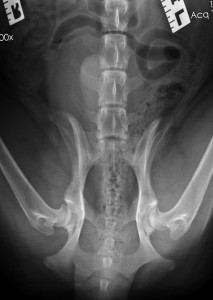

Hip dysplasia is common. It frequently becomes apparent from 6 months or so of age, leading to serious pain when the hip is extended.

Neurectomy involves surgically damaging the sensory innervation to the affected hip(s) joint capsule. It doesn’t further destabilise the articulation (like a femoral head and neck excision would – see the separate article on this surgery). Neurectomies can be done on both sides simultaneously, and costs are much less than for THR. No special aftercare is required other than to protect the overlying soft tissue wound while it heals in the two weeks post-op. The risk of significant adverse complications with neurectomy is low. The rest of the innervation to the hindlimb(s) is intact, and there is no adverse functional significance from the dog’s point of view in losing the sensation to the hip joint.